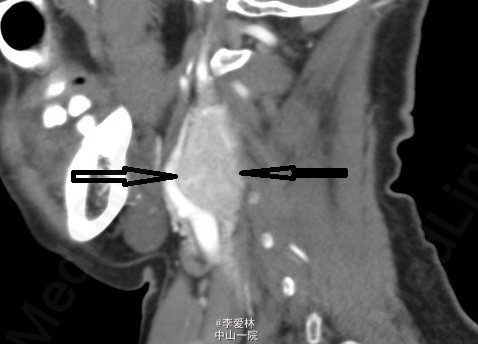

患者半年余前无明显诱因发现左侧颈部肿物,无伴局部红、肿、热、痛,无吞咽困难,呼吸困难,无头晕、头痛等不适。当时未予重视。近2月来,肿物进行性增大,遂至广州市中西医结合医院就诊,查颈部MRI平扫示:1、左侧颈动脉鞘内占位性病变,考虑为颈动脉体瘤可能性大,不排除神经源性肿瘤;2、双侧颌下腺旁多发淋巴结肿大;MRI增强示:左侧颈内外动脉分叉处明显分离,结合平扫片考虑为左侧颈动脉体瘤。 查体: 左颈部近下颌处可见突起肿物,饱满、膨隆,范围大约3*4cm,可触及搏动,与心率搏动频率相同,无压痛,隆起皮肤皮温正常,感觉良好,未见红肿,听诊未闻及震颤,无传导,锁骨无压痛叩击痛,连续性完好,左肩关节活动良好,左上肢感觉完好。无伸舌偏斜,额纹、鼻唇沟双侧对称 入院后诊断“颈动脉体瘤”明确,择期行颈动脉体瘤切除术,术后病理提示颈动脉体瘤。术后患者恢复可,无围手术期并发症。 颈动脉体瘤发病率较低,通常表现为颈部无痛性包块,容易与颈淋巴结结核、转移性肿瘤、神经源性肿瘤等相混淆。再加上血管外科在中国起步较晚,对于该类病人,笔者在临床上也曾听闻在基层医院有直接穿刺活检或者切开而导致大出血的,也遇到一些病例收住在耳鼻喉科的。对于颈部包块的患者,尤其是有搏动感的患者,应该引起警惕,予以颈部及甲状腺彩超是比较明智的选择。 颈动脉体瘤的治疗,以手术为主,由于颈动脉体瘤绝大多数都是良性的,所以术后复发、转移的风险较低,对于没有家族史的患者,除非再次出现颈部包块或者神经压迫症状,否则可以不要求密切随访。 入院检查如图所示(CTA) ,术后病理如图